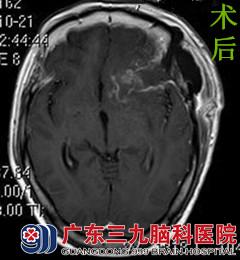

于是,曾阿姨一家人来到广东三九脑科医院,行头颅MR检查提示左侧额部示一团块状异常信号影,病变宽基底与前颅底相连,大小约4.87cmX3.87cmX2.70cm,邻近脑组织受压推移。左侧侧脑室受压明显变窄,中线结构向右偏移。完善相关检查后,由综合神经外科的鲁明主任主刀,在全麻下行左侧蝶骨嵴脑膜瘤切除术,术中显微镜下见灰白色肿瘤组织位于左侧鞍旁蝶骨嵴区,分块全切肿瘤,术中视神经、动眼神经、颈内动脉及其分支血管保护完好,手术顺利结束,术后患者未出现任何手术并发症,经系统治疗后康复出院。术后病理结果为:过渡型脑膜瘤(WHO I级)。